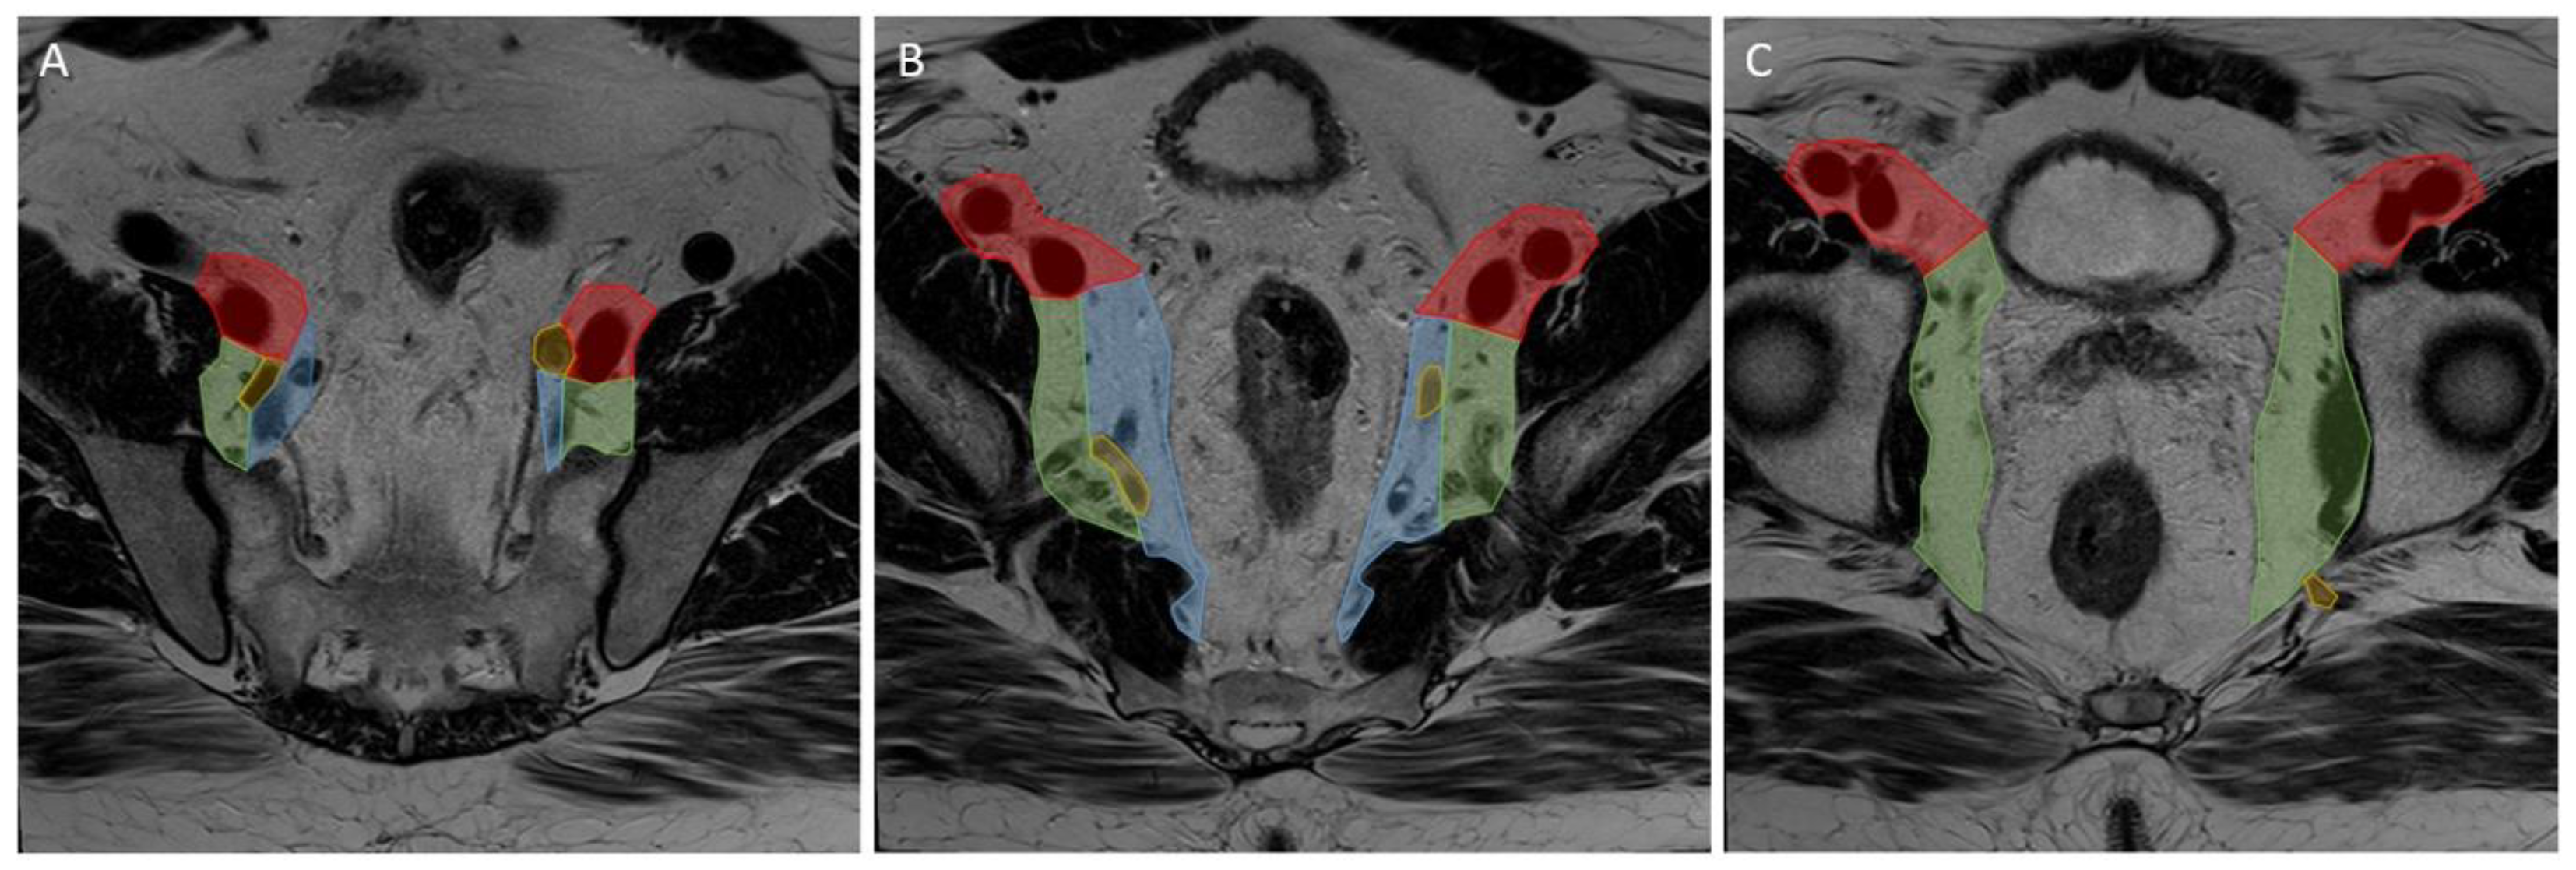

2.3. Image Segmentation